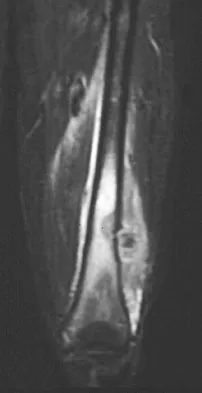

A healthy 16-year-old boy has had increasing pain in the right knee for the past 3 months. Examination reveals warmth and swelling around the distal femur. Radiographs and an MRI scan are shown in Figures 51a through 51c, and a biopsy specimen is shown in Figure 51d. What is the most likely diagnosis?

Explanation

The radiographs show a bone-producing lesion in the distal femoral metaphysis in this case of classic osteosarcoma presenting in the most common location, the distal femur. The coronal MRI scan reveals a marrow-occupying lesion with extension into the soft tissues. The histology shows osteoid production by pleomorphic cells consistent with an osteosarcoma. Ewing's sarcoma is a bone tumor characterized by uniform small blue cells on histology. Rhabdomyosarcoma is the most common childhood soft-tissue sarcoma. Osteomyelitis has an inflammatory appearance on histology. Malignant fibrous histiocytoma of bone has a lytic radiographic appearance and a pleomorphic storiform pattern without osteoid on histology. Wold LE, Adler CP, Sim FH, et al: Atlas of Orthopedic Pathology, ed 2. Philadelphia, PA, WB Saunders, 2003, p 179.